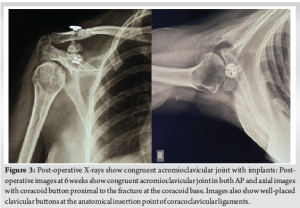

A 48-year-old female presented to the emergency room with a complaint of a fall from a height. Following the incident, the patient experienced retrograde amnesia and substantial pain in her right shoulder and hand while moving. Upon arrival, she was hemodynamically stable but was in significant discomfort. She was initially diagnosed with a right coracoid fracture and had a history of rheumatoid arthritis, for which she was receiving long-term treatment with hydroxychloroquine. During the initial evaluation, she had tenderness around the coracoid process of the right shoulder with severe painful restriction of shoulder movements. She also had symptoms and signs suggestive of a concussion injury to the brain. She had normal systemic examinations. Radiological investigations included a magnetic resonance imaging (MRI) of the cervical spine, revealing straightening due to paraspinal muscle spasm and mild posterior bulging of the C3-C6 discs without significant foraminal compromise. A computed tomography (CT) scan of the brain ruled out acute intracranial pathology. A CT scan of the thorax identified a displaced coracoid process fracture, and a right shoulder CT confirmed a double fracture of the coracoid process. However, the associated ACJ dislocation was left undiagnosed in the initial evaluation. The patient was managed conservatively with standard analgesia and a shoulder immobilizer. Despite adherence to conservative treatment, persistent pain and functional limitations were noted in subsequent follow-ups. A 6-week follow-up X-ray revealed non-union of the coracoid fracture along with ACJ dislocation, which had been previously undiagnosed. Further evaluations showed significant shoulder instability, persistent pain, and muscle wasting, with restricted movements in forward flexion, abduction, and external rotation.(Fig. 1 ). An MRI of the right shoulder later confirmed an anteroinferior labral tear, a small Hill-Sachs lesion, and ACJ dislocation. A fresh CT scan showed a double fracture of the coracoid extending to the base with superior displacement of the ACJ. Multiple ipsilateral rib fractures were also identified. Given the failed conservative management, a multidisciplinary team recommended surgical intervention.(Fig. 2 )